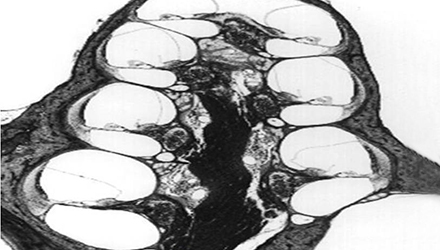

3、膜迷路破滅

膜迷路積水致膜迷路脹破,內(nèi)外淋巴液混合,刺激神經(jīng)感覺(jué)細(xì)胞導(dǎo)致眩暈、耳鳴、耳聾,裂口愈合則病變暫時(shí)恢復(fù)。下圖左為前庭膜膨大,右圖為前庭膜破裂,內(nèi)外淋巴交混。